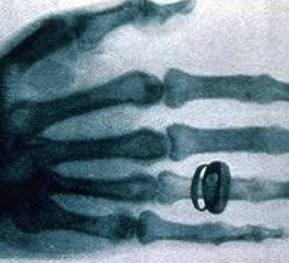

圖像監控法是直接從x射線透視圖像構形來判斷物品的,因此,被檢物是否可疑,取決于監視器或顯示器上的圖像。顯示器或監視器上出現的不常見物或異形物,都應視為可疑物品。那些不能準確辨認的物品也應視為可疑物品,需仔細觀察,根據需要可將圖像定位分析。